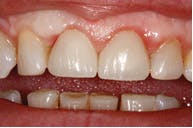

Figure 5: Complete with e.max crowns

Solea's precision and ability to maintain a clean surgical site allowed this unscheduled procedure to be completed successfully. Additionally, rapid healing was observed (figure 3). With Solea, this was a minimally invasive procedure and crowns were prepared 30 days postoperatively (figure 5). Traditional surgery would require six to eight weeks until proper conditions were established for definitive restorative work. In addition, there would have been more postoperative pain and slower healing with traditional instruments.